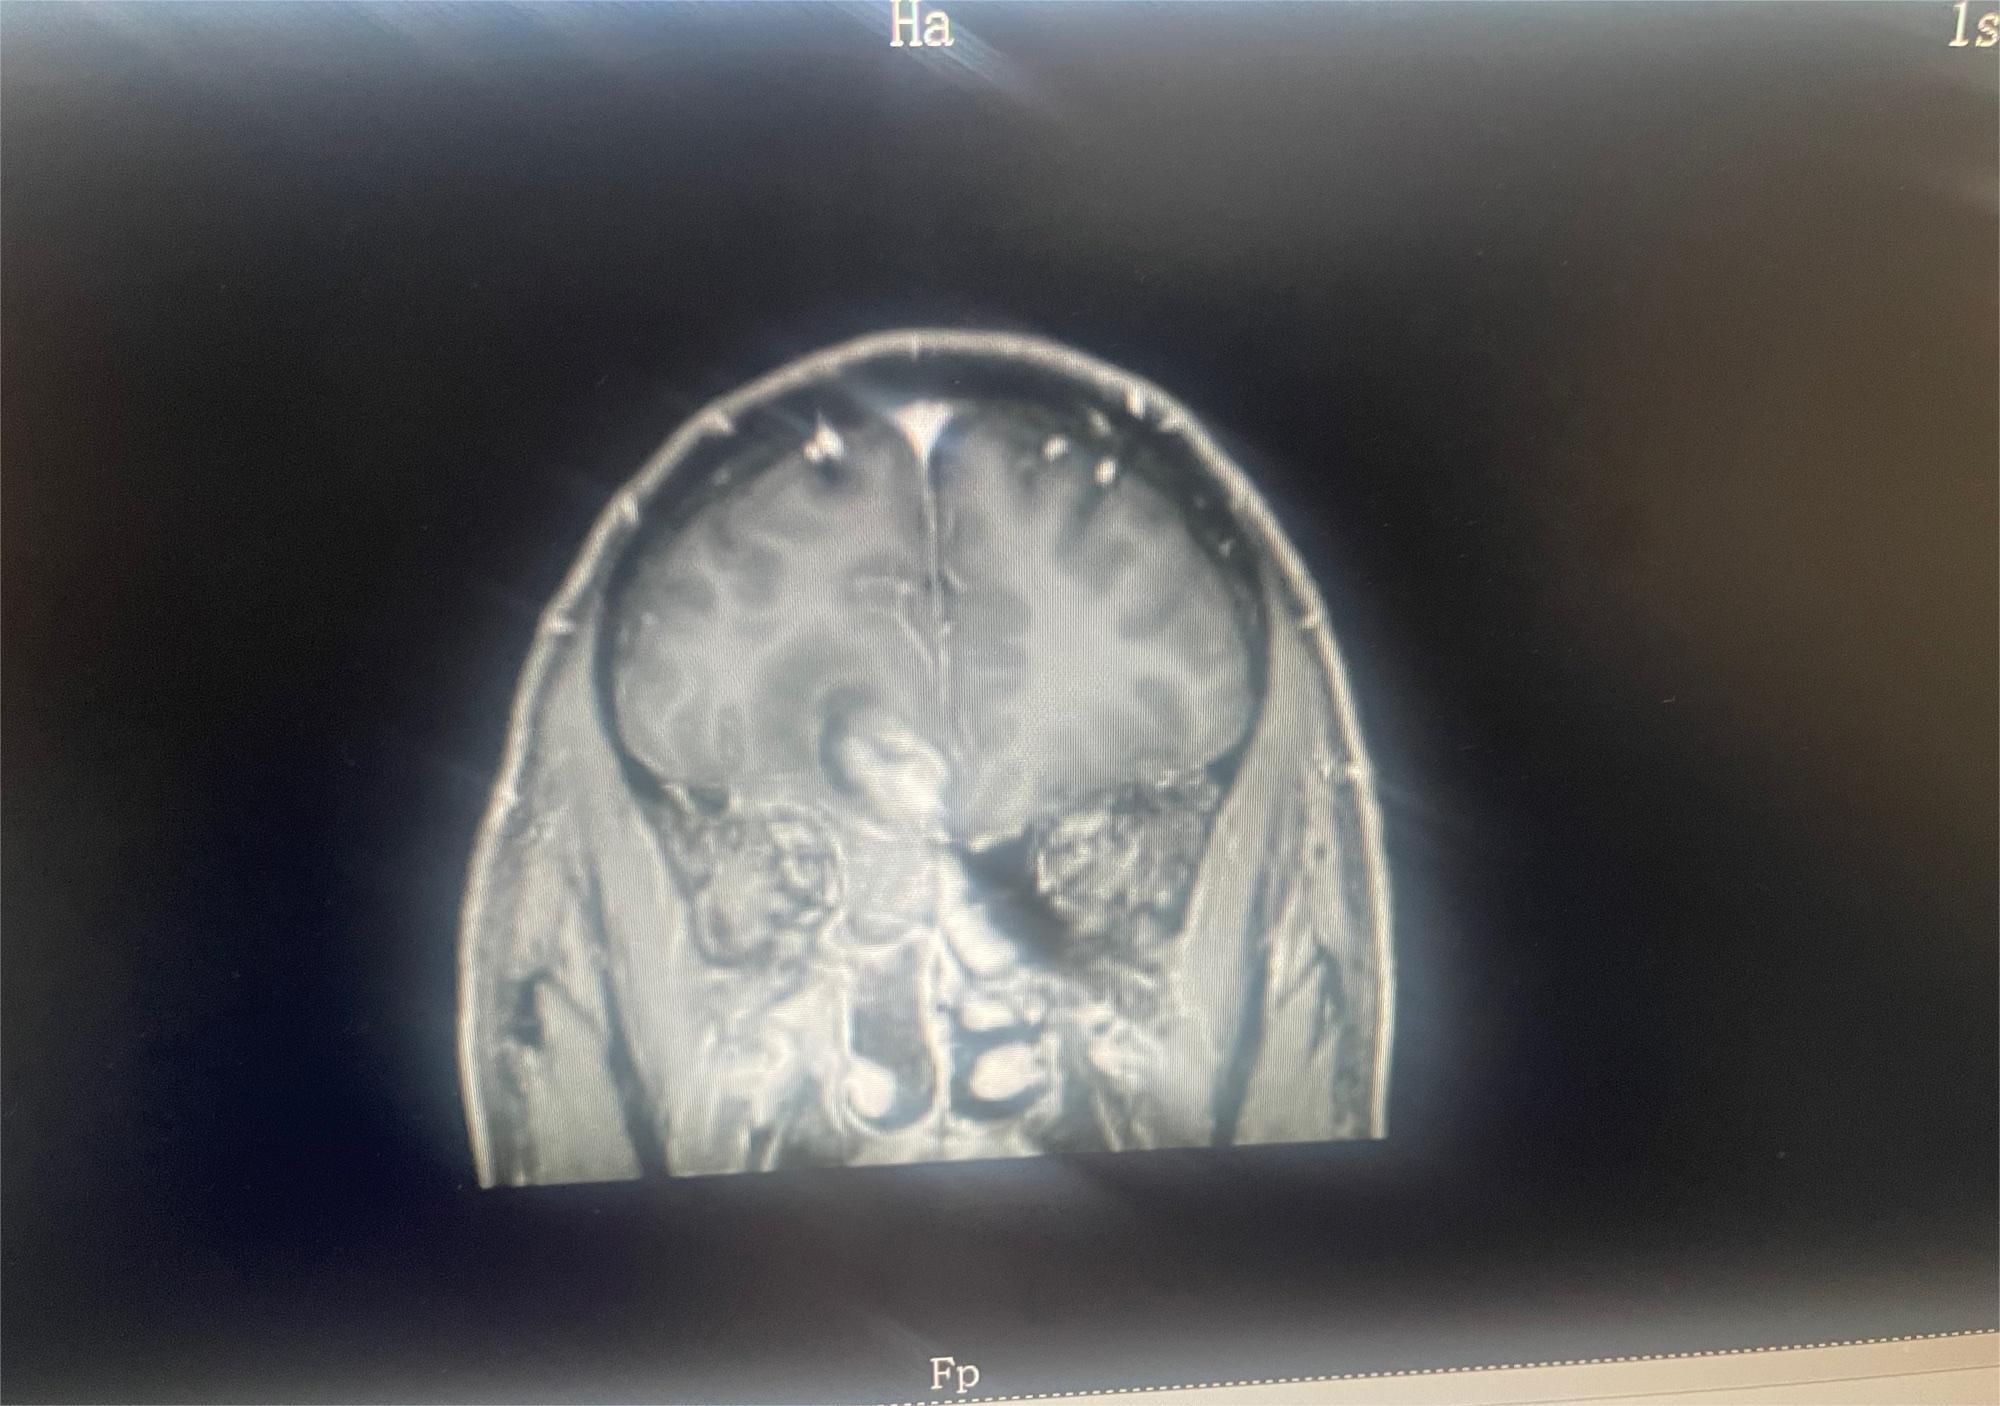

O=O 02023-08-02 患者家属这是我83岁奶奶的报告,哪位朋友能帮忙看看这是到什么阶段了,发展到晚期还有多长时间。 医生说肿瘤挨着血管,做不了手术,年...